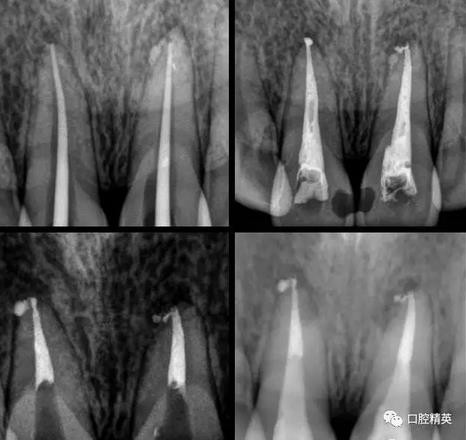

處理:(初診)取原始模型,11,21開髓,拔髓,擴(kuò)根,沖洗,CP碘仿棉捻開放。

(二診)取出開放物,雙氧水沖洗,氫氧化鈣糊劑加碘仿暫封2周。

(三診) 去除暫封物及糊劑,鹽水沖洗,隔濕,干燥,大錐度牙膠尖配合樹脂根充糊劑行根管充填,一周后復(fù)診。

(四診)11,21唇側(cè)膿腫基本消除,叩(-),預(yù)備樁道,置入纖維樁,備牙,取模,翻制臨時(shí)冠。

術(shù)中根管治療,置人纖維樁,牙體預(yù)備,臨時(shí)冠修復(fù)